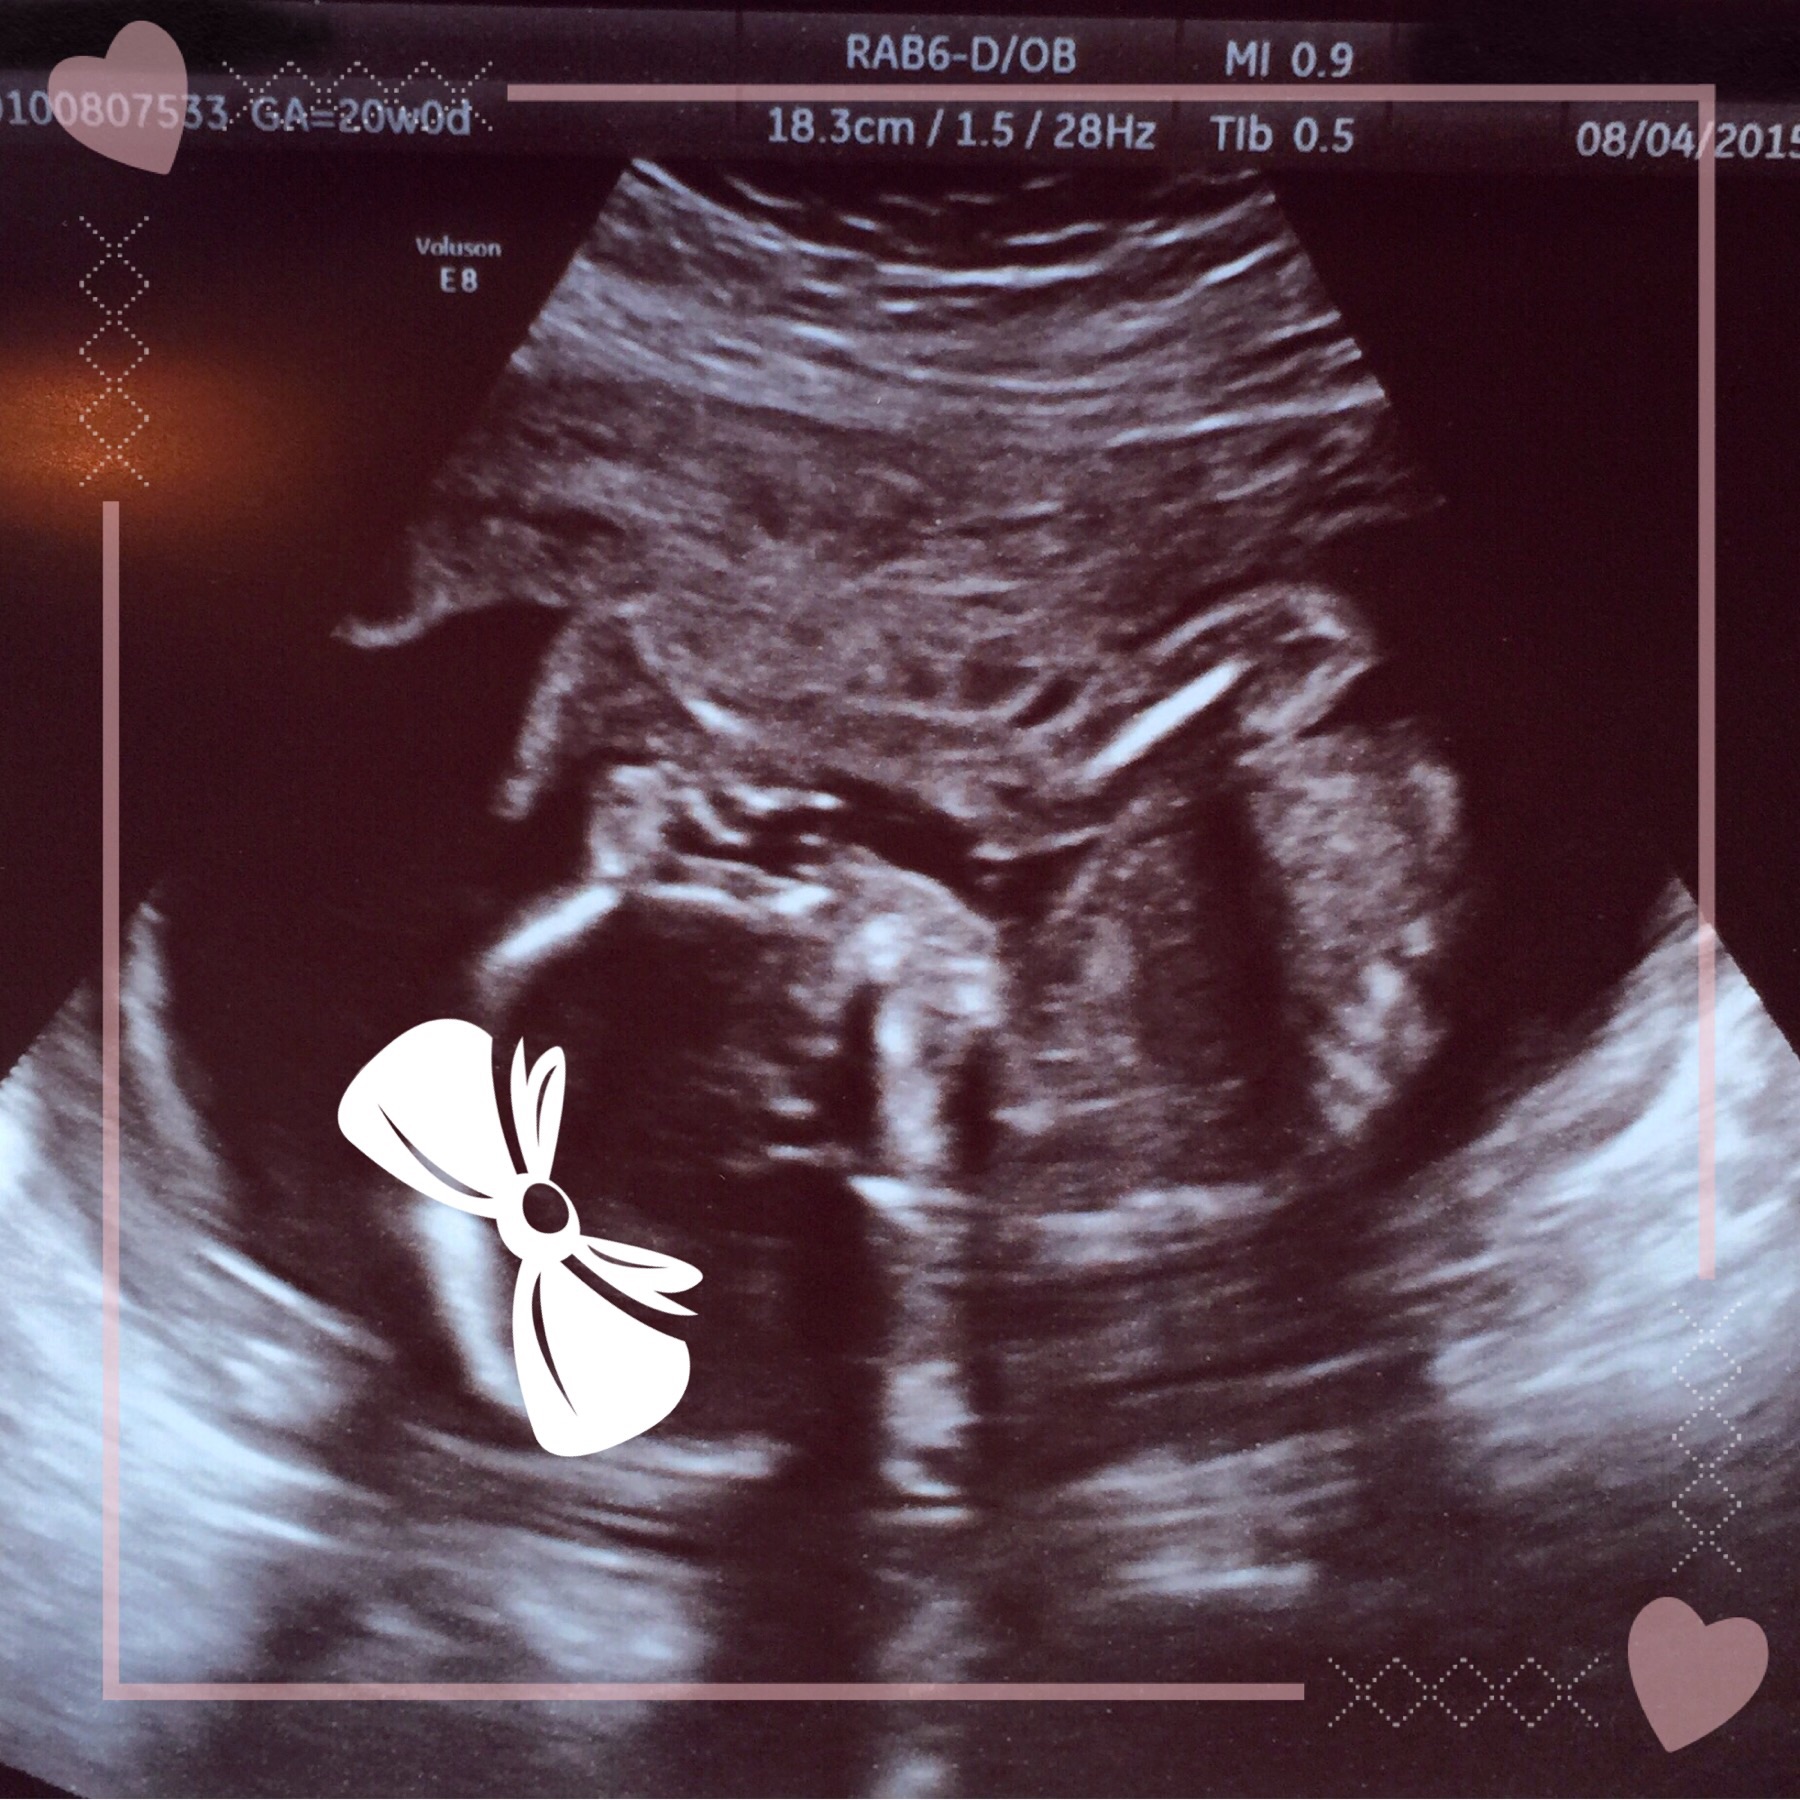

• Just had my Anatomy scan this past Tuesday (8/4/15 - 20.0 weeks). So far, so good! Today I am 20.3 weeks.

• We had a great scan today, everything was beautiful and perfect. Team green <3